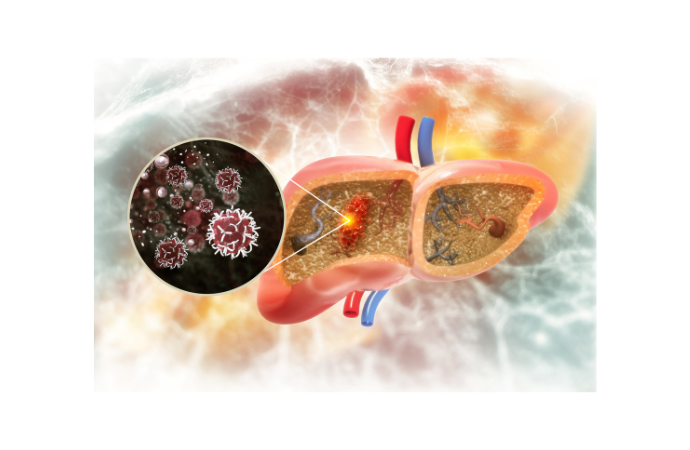

Deep Learning for Liver Cyst Segmentation in ADPKD Patients

Autosomal dominant polycystic kidney disease (ADPKD) is a common inherited kidney disorder affecting millions globally, often accompanied by polycystic liver disease (PLD). PLD, characteris